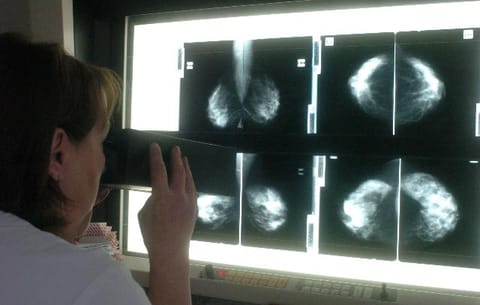

Egy nemzetközi kutatócsoport átfogó képet festett a melldaganatok trendjei és egy adott ország fejlettségének kapcsolatáról. Adataik óriási szakadékot mutatnak a túlélési arányokban, attól függően, ki, hol él.